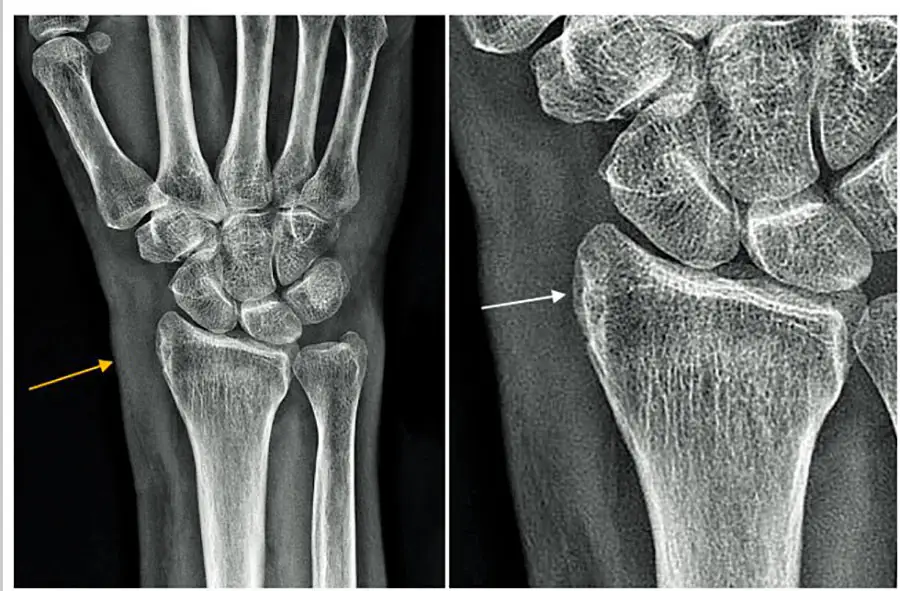

Результаты рентгенографии — на фоне локальной остеопении шиловидного отростка лучевой кости слабо выраженное прилегание надкостницы (белая стрелка) и отек мягких тканей (желтая стрелка).

Заключение: Рентгенологические признаки теносиновита Де Кервена.